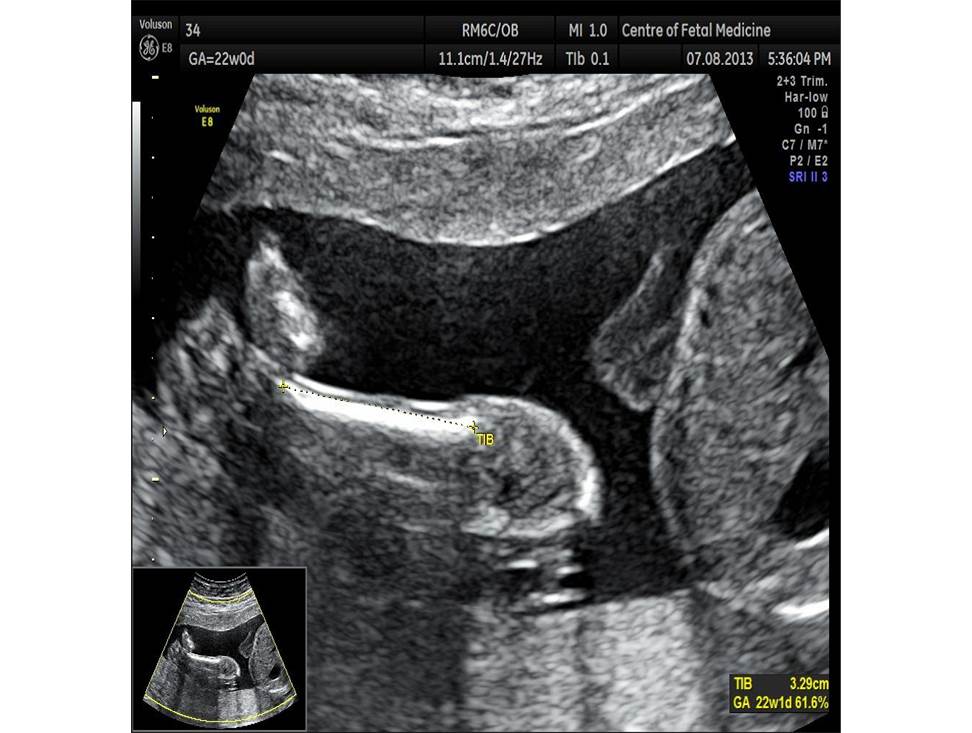

Вопрос 5

Проанализируйте изображения плода в 22 недели и установите диагноз